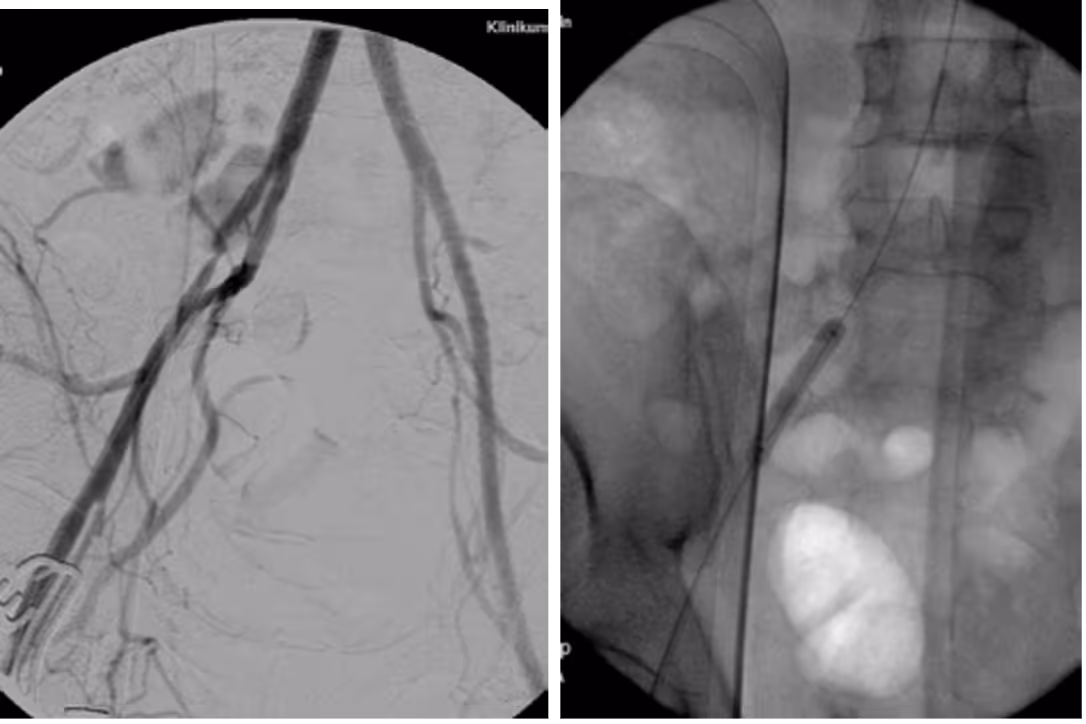

Many peripheral stenoses and occlusions are accessible by endovascular means. Among the endovascular procedures treatment of iliac and femoro-popliteal stenoses/occlusions are the most often used techniques. Thorough planing, proper use of endovascular tools and adherence to meticulous endovascular techniques are therefore of upmost importance for the success.